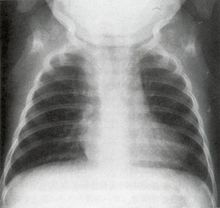

法洛四联症(tetralogyofFallot)因Fallot首先描述而得名,又称发绀四联症,是联合的先天性心脏血管畸形,本病包括室间隔缺损,肺动脉口狭窄,主动脉右位(骑跨于缺损的心室间隔上)和右心室肥厚,其中前两种畸形为基本病变,本病是最常见的紫绀型先天性心脏血管病。只有心室间隔缺损、肺动脉口狭窄和右心室肥大而无主动脉骑跨的病人,被称为非典型的法乐四联症。发病率约占先心病的11%~13%,男女比例相仿。

本病临床表现较具特征性,一般不难诊断,但需与其它有紫绀的先天性心脏血管病相 鉴别。(一)肺动脉口狭窄合并心房间隔缺损伴有右至左分流(法乐三联症)本病紫绀出现较晚。胸骨左缘第二肋间的收缩期杂音较响,所占据时间较长,肺动脉瓣区第二心音减轻、分裂。X线片上见心脏阴影增大较显著,肺动脉总干弧明显凸出。心电图中右心室劳损的表现较明显。右心导管检查、选择性指示剂稀释曲线测定或选择性心血管造影,发现肺动脉口狭窄属瓣膜型,右至左分流水平在心房部位,可以确立诊断。(二)艾森曼格综合征心室间隔缺损、心房间隔缺损、主动脉-肺动脉间隔缺损或动脉导管未闭的病人发生严重肺动脉高压时,使左至右分流转变为右至左分流,形成艾森曼格综合征。本综合征紫绀出现晚;肺动脉瓣区有收缩喷射音和收缩期吹风样杂音,第二心音亢进并可分裂,可有吹风样舒张期杂音;X线检查可见肺动脉总干弧明显凸出,肺门血管影粗大而肺野血管影细小;右心导管检查发现肺动脉显著高压等,可资鉴别。(三)埃勃斯坦畸形和三尖瓣闭锁埃勃斯坦畸形时,三尖瓣的隔瓣叶和后瓣叶下移至心室,右心房增大,右心室相对较小,常伴有心房间隔缺损而造成右至左分流。心前区常可听到4个心音;X线示心影增大,常呈球形,右心房可甚大;心电图示右心房肥大和右束支传导阻滞;选择性右心房造影显示增大的右心房和畸形的三尖瓣,可以确立诊断。三尖瓣闭锁时三尖瓣口完全不通,右心房的血液通过未闭卵圆孔或心房间隔缺损进入左心房,经二尖瓣入左心室,再经心室间隔缺损或未闭动脉导管到肺循环。X线检查可见右心室部位不明显,肺野清晰。心电图有左心室肥大表现。选择性右心房造影可确立诊断。

辅助检查

(三)超声心动图检查见主动脉根部扩大,其位置前移并骑跨在心室间隔上,主动脉前壁与心室间隔间的连续性中断,该处室间隔回声失落,而主动脉后壁与二尖瓣则保持连续,右心室肥厚,其流出道、肺动脉瓣或肺动脉内径狭窄。超声造影法还可显示右心室到主动脉的右至左分流。(五)心脏导管检查右心导管检查可有下列发现:1.肺动脉口狭窄引起的右心室与肺动脉间收缩压阶差,分析压力曲线的形态,可帮助判定狭窄的类型。2.心导管可能由右心室直接进入主动脉,从而证实有骑跨的主动脉和心室间隔缺损。(六)选择性指示剂稀释曲线测定通过右心导管分别向右心房、右心室和肺动脉注射指示剂(染料或维生素C等),在周围动脉记录指示剂稀释曲线(用耳血氧计或铂电极系统等),可见在右心室及其上游心腔注入指示剂时记录到出现时间短、曲线降支呈双峰的右至左分流曲线,而在肺总动脉及其下游注入指示剂时则记录到正常曲线,从而定出右至左分流的部位。